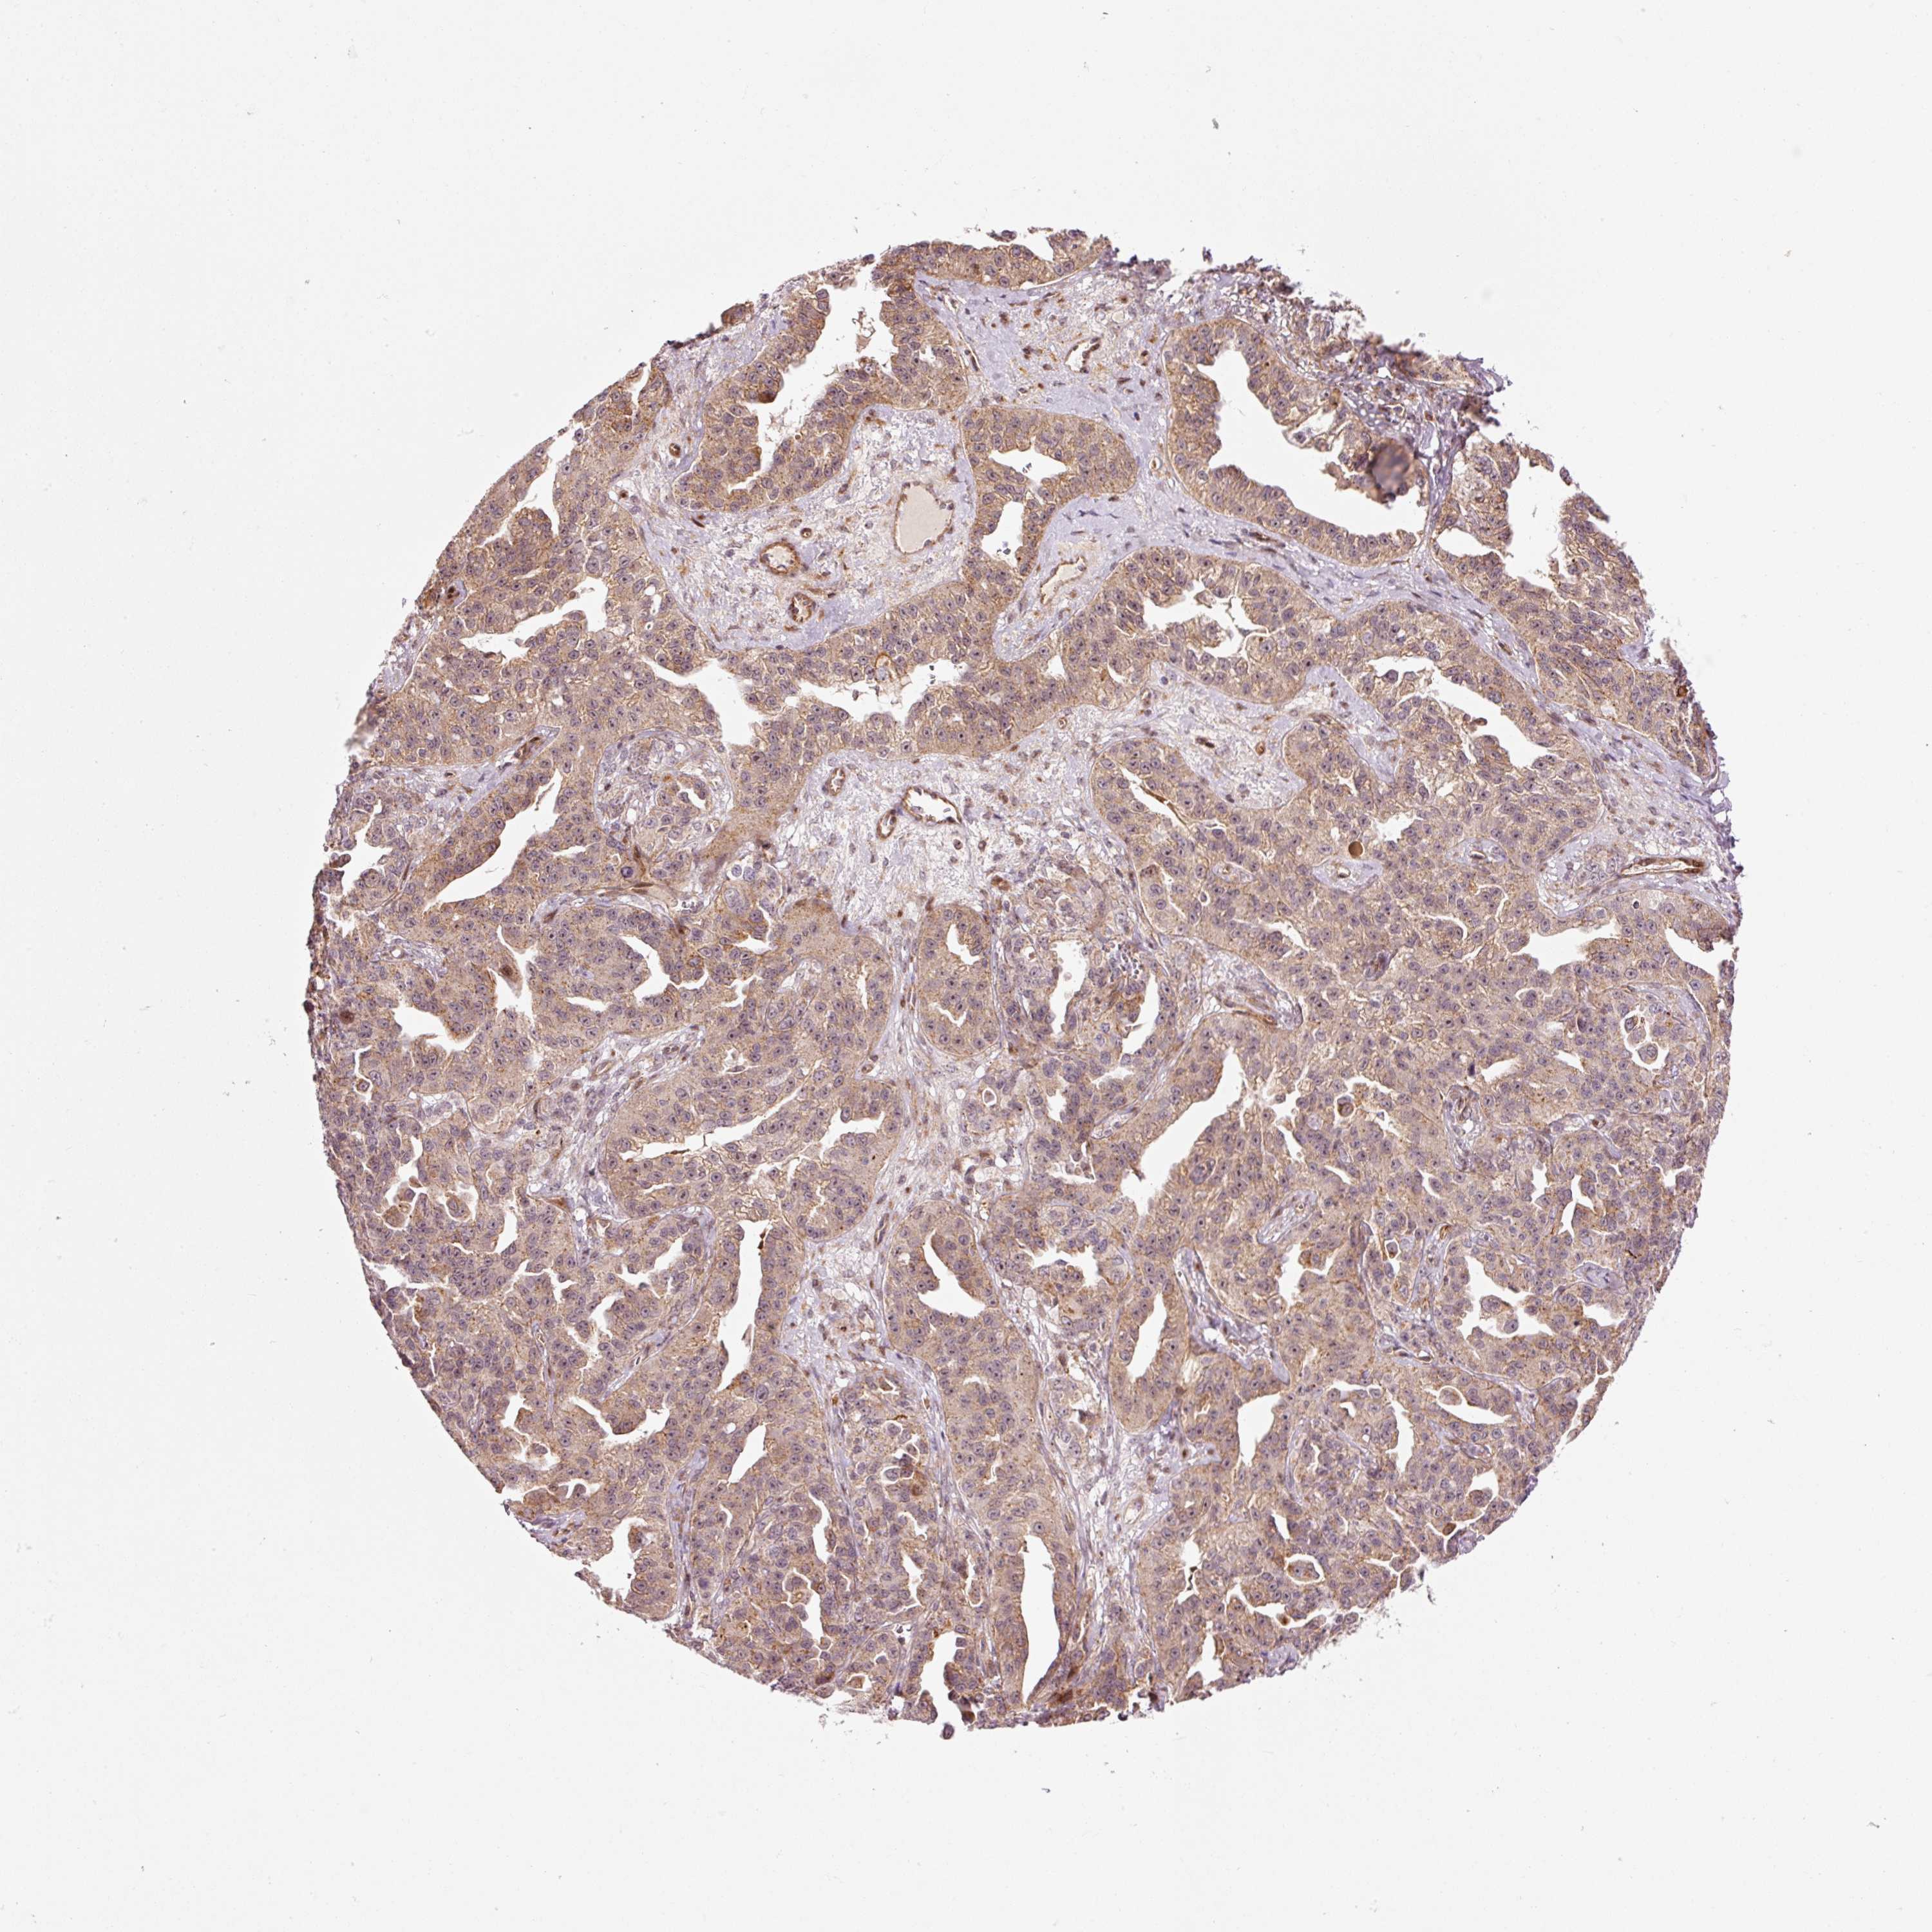

OVARIAN CANCER - Protein expressioni

A mouse-over function shows sample information and annotation data. Click on an image to view it in a full screen mode. Samples can be filtered based on level of antibody staining by selecting one or several of the following categories: high, medium, low and not detected. The assay and annotation is described here.

Note that samples used for immunohistochemistry by the Human Protein Atlas do not correspond to samples in the TCGA dataset.

Antibody stainingi

Antibody staining in the annotated cell types in the current human tissue is reported as not detected, low, medium, or high, based on conventional immunohistochemistry profiling in selected tissues. This score is based on the combination of the staining intensity and fraction of stained cells.

Each image is clickable and will lead to virtual microscopy that enables deeper exploration of all samples and also displays staining intensity scores, fraction scores and subcellular localization as well as patient and tissue information for each sample.

Cystadenocarcinoma, serous, NOS